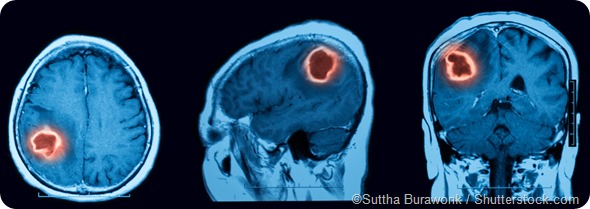

MRI scan cerebral hemorrhage